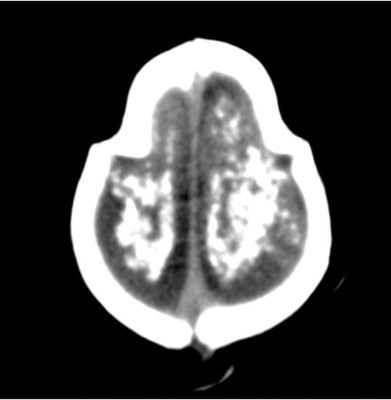

Un grupo de investigadores brasileños difundieron un estudio que revela imágenes computarizadas, resonancias magnéticas y ultrasonidos, de bebés y fetos infectados con el virus del zika, evidenciando que el daño al cerebro de los menores es mucho mayor del que se anticipaba.

La radióloga brasileña Fernanda Tovar-Moll, que participó en la investigación publicada en la revista Radiology, afirmó que 'hay bebés con cabezas de tamaño normal, pero con cerebros que no lo son. Hay bebés que donde debía haber un cerebro ahora hay solo líquido y casi no tienen tejido cerebral. La microcefalia es solo la punta del iceberg'.

Las imágenes muestran el efecto devastador que la microcefalia causa en los cerebros de los menores. En algunos casos, los cráneos de los bebés colapsaron debido a que el cerebro dejó de crecer.

En varios de los bebés examinados, la escala de severidad del daño variaba de mayor a menor. Los exámenes mostraron que varios de los pacientes tenían afectado el cerebelo, clave para el movimiento, equilibrio y habla. Varios bebés también tenían problemas para tragar y comer.

En la imagen un feto de 24 semanas de gestación muestra el cráneo colapsado, luego de que su cerebro dejará de crecer a causa del virus del zika.

Esta radiografía muestra el cerebro de un feto afectado a las 20 semanas de gestación.